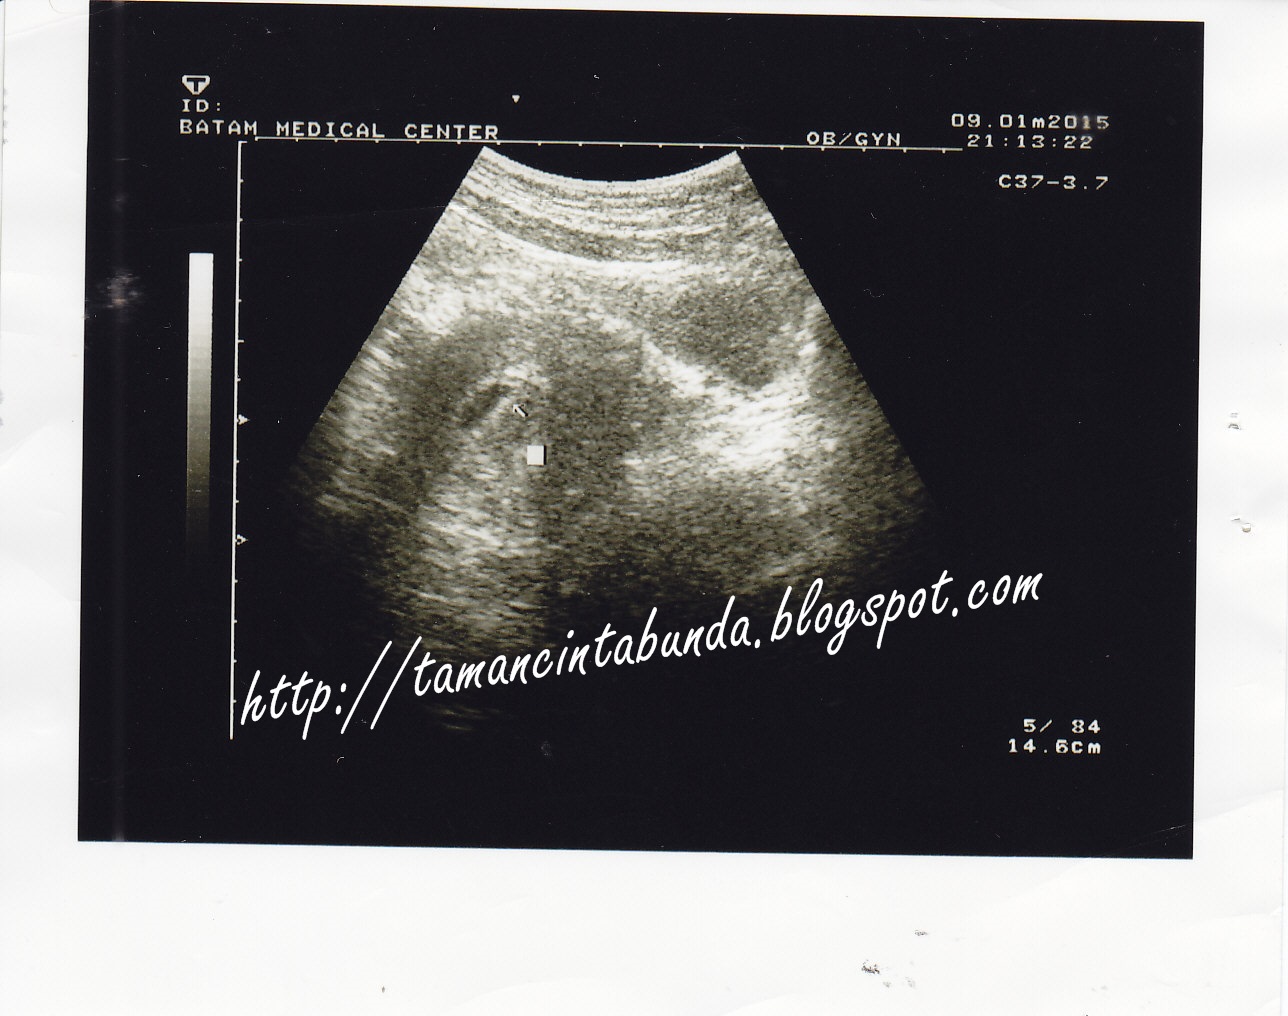

Kira-kira 1 minggu setelahnya, tepatnya tanggal 9 Januari

2015 bun mengajak ayah untuk pergi ke dokter kandungan. Dokter ini salah satu

dokter yang terkenal di Batam dan banyak sekali pasiennya sehingga kalau memang

mau periksa dan konsultasi, ya musti sabar. Sejak jauh sebelum kehamilan bun

kali ini, bun sudah berniat, jikalau hamil kedua nanti, bun ingin ke beliau. Beliau

adalah Dr. Adriyanti, SpOG yang berpraktek di RSOB dan memiliki klinik BMC. Sedikit

| Masih bentuk kecil |